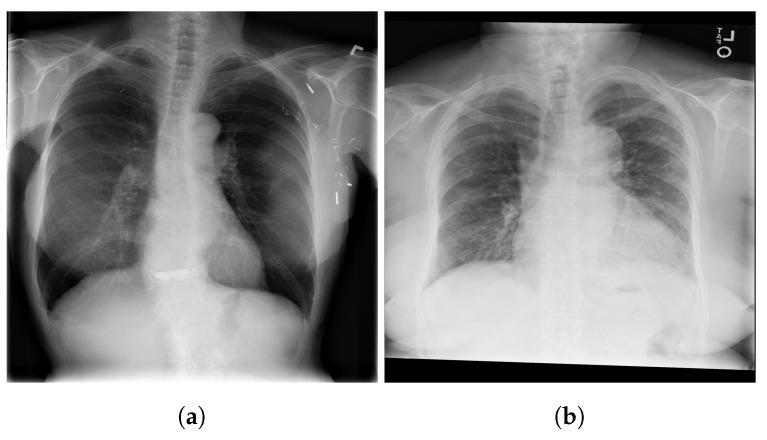

COVID-19,which is caused by the severe acute respiratory syndrome coronavirus 2 (SARS-CoV-2), is one of the worst pandemics in recent history. The identification of patients suspected to be infected with COVID-19 is becoming crucial to reduce its spread. We aimed to validate and test a deep learning model to detect COVID-19 based on chest X-rays. The recent deep convolutional neural network (CNN) RegNetX032 was adapted for detecting COVID-19 from chest X-ray (CXR) images using polymerase chain reaction (RT-PCR) as a reference. The model was customized and trained on five datasets containing more than 15,000 CXR images (including 4148COVID-19-positive cases) and then tested on 321 images (150 COVID-19-positive) from Montfort Hospital. Twenty percent of the data from the five datasets were used as validation data for hyperparameter optimization. Each CXR image was processed by the model to detect COVID-19. Multi-binary classifications were proposed, such as: COVID-19 vs. normal, COVID-19 + pneumonia vs. normal, and pneumonia vs. normal. The performance results were based on the area under the curve (AUC), sensitivity, and specificity. In addition, an explainability model was developed that demonstrated the high performance and high generalization degree of the proposed model in detecting and highlighting the signs of the disease. The fine-tuned RegNetX032 model achieved an overall accuracy score of 96.0%, with an AUC score of 99.1%. The model showed a superior sensitivity of 98.0% in detecting signs from CXR images of COVID-19 patients, and a specificity of 93.0% in detecting healthy CXR images. A second scenario compared COVID-19 + pneumonia vs. normal (healthy X-ray) patients. The model achieved an overall score of 99.1% (AUC) with a sensitivity of 96.0% and specificity of 93.0% on the Montfort dataset. For the validation set, the model achieved an average accuracy of 98.6%, an AUC score of 98.0%, a sensitivity of 98.0%, and a specificity of 96.0% for detection (COVID-19 patients vs. healthy patients). The second scenario compared COVID-19 + pneumonia vs. normal patients. The model achieved an overall score of 98.8% (AUC) with a sensitivity of 97.0% and a specificity of 96.0%. This robust deep learning model demonstrated excellent performance in detecting COVID-19 from chest X-rays. This model could be used to automate the detection of COVID-19 and improve decision making for patient triage and isolation in hospital settings. This could also be used as a complementary aid for radiologists or clinicians when differentiating to make smart decisions.